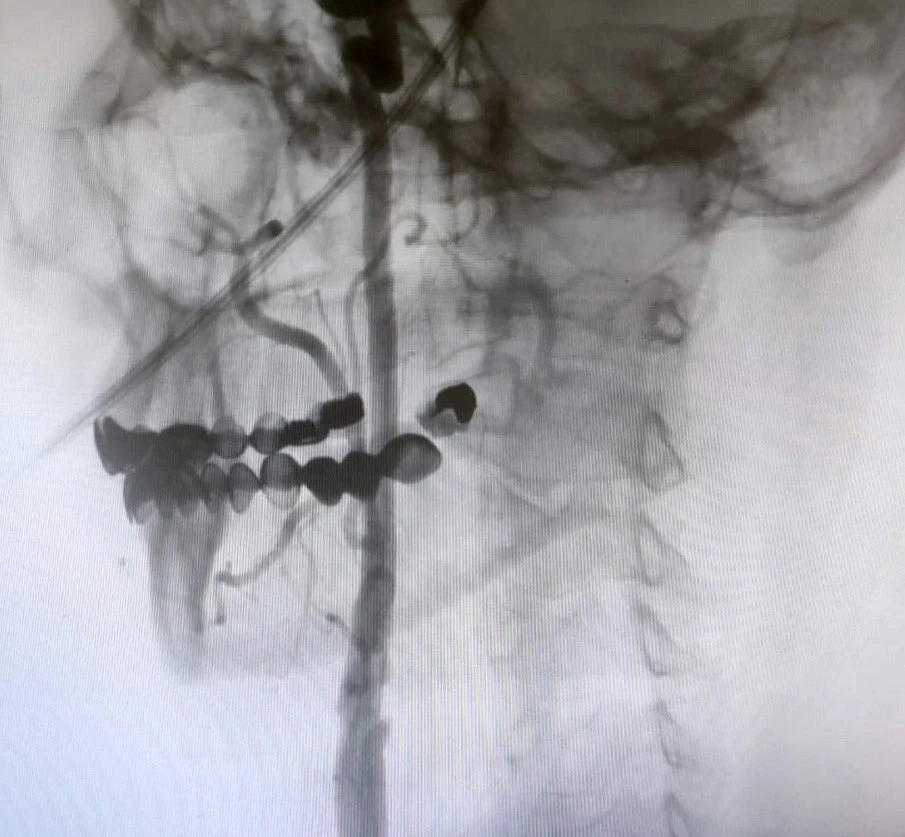

"Boyun damarlarını açma işlemi iki şekilde yapılabilir. Bir karotis endarterektomi dediğimiz ameliyatla bir diğer yöntem ise perkutan girişim dediğimiz stent yöntemiyle açılabilir. Biz kliniğimizde nöroloji ve kardiyoloji olarak bir konsey yapıyoruz. Damarı ciddi tıkalı olan ve buna bağlı felç geçirmiş hastalarda bu konseyde hastaya işlem yapıp yapmama kararı veriyoruz. Verdiğimiz karar çerçevesinde eğer hastaya işlem kararı vermişsek femoral arter dediğimiz kasık arterinden bir şitle 6 ya da 7 F çapında bir şitle ince bir boruyla bu damara giriş yapıyoruz ve boyun damarlarına ulaşıyoruz. Özellikle teller, filtreler ve stentlerle bu damarları açıp hastanın tedavisini gerçekleştiriyoruz. İşlem ameliyatsız olduğu için hastamız ertesi gün rahat bir şekilde problem olmazsa işlemde taburcu olabiliyor bu işlemden sonra. Bu işlemin yapılması için özellikle anjiografinin olduğu girişimsel nöroloji uzmanının ve girişimsel kardiyoloji uzmanının olduğu ve bu konuda yeterli vaka tecrübesine ve deneyime sahip uzmanların olduğu merkezler gerekir. Bunu yapabilmek için belli bir vaka sayısına ulaşmak ve bu konuda tecrübeli olmak gerekiyor. Biz de Manisa Şehir Hastanesi’ndeki girişimsel kardiyoloji ve nöroloji uzmanları olarak bu işlemi kliniğimizde efektif bir şekilde gerçekleştiriyoruz."